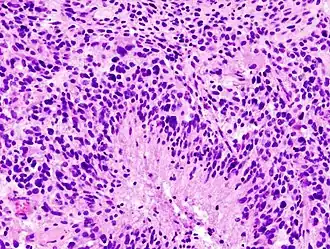

Виды астроцитом[3]

.jpg)

- Пилоцитарная астроцитома (I степень злокачественности) — доброкачественная опухоль с четкими границами, растет медленно. Чаще встречается у детей. В основном локализируется в мозжечке, стволе мозга и зрительных нервах.

- Фибриллярная астроцитома (II степень злокачественности) — опухоль без четких границ, растет медленно. Встречается у больных 20-30 лет.

- Анапластическая астроцитома (III степень злокачественности) — злокачественная опухоль без четких границ, растет быстро, прорастает в мозговую ткань. Возраст у больных 30—50 лет, чаще болеют мужчины.

- Глиобластома (IV степень злокачественности) — наиболее злокачественная опухоль без четких границ, растет очень быстро, прорастает в мозговую ткань. Возраст у больных 40—70 лет, чаще болеют мужчины[4].